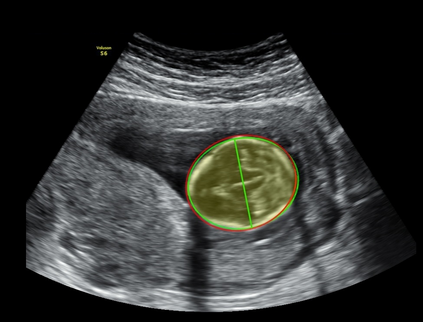

In this paper, we propose an end-to-end multi-task neural network called FetalNet with an attention mechanism and stacked module for spatio-temporal fetal ultrasound scan video analysis. Fetal biometric measurement is a standard examination during pregnancy used for the fetus growth monitoring and estimation of gestational age and fetal weight. The main goal in fetal ultrasound scan video analysis is to find proper standard planes to measure the fetal head, abdomen and femur. Due to natural high speckle noise and shadows in ultrasound data, medical expertise and sonographic experience are required to find the appropriate acquisition plane and perform accurate measurements of the fetus. In addition, existing computer-aided methods for fetal US biometric measurement address only one single image frame without considering temporal features. To address these shortcomings, we propose an end-to-end multi-task neural network for spatio-temporal ultrasound scan video analysis to simultaneously localize, classify and measure the fetal body parts. We propose a new encoder-decoder segmentation architecture that incorporates a classification branch. Additionally, we employ an attention mechanism with a stacked module to learn salient maps to suppress irrelevant US regions and efficient scan plane localization. We trained on the fetal ultrasound video comes from routine examinations of 700 different patients. Our method called FetalNet outperforms existing state-of-the-art methods in both classification and segmentation in fetal ultrasound video recordings.